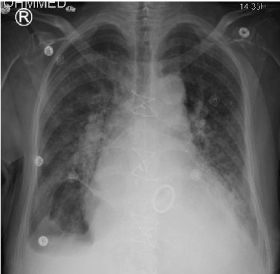

1.88 mg/dL and GFR cytatin was 21. Chest x ray showed pulmonary edema (Figure 1).

Figure 1. Chest X ray; Pulmonary edema.